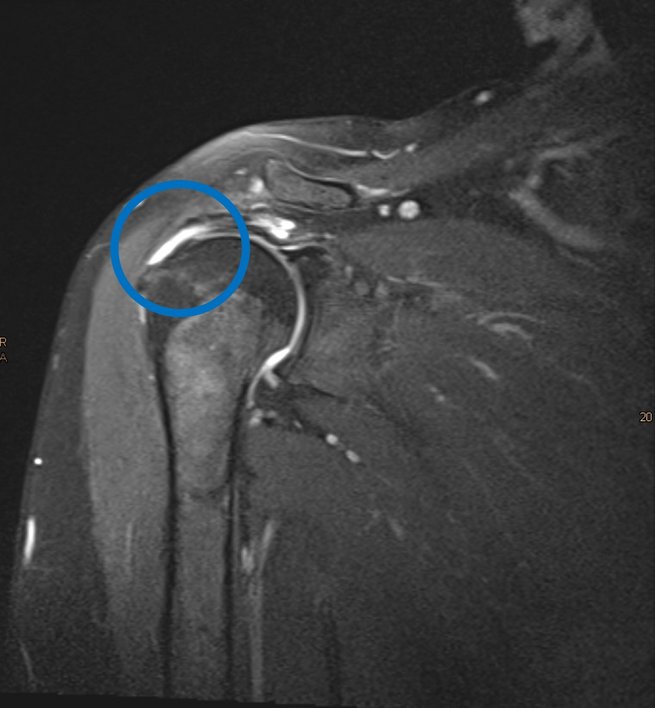

Beispiel einer 55-jährigen Patientin mit kompletter Ruptur der Rotatorenmanschette (Supraspinatussehne)

Bei einer Rotatorenmanschettenruptur ist eine oder mehrere Sehnen der sogenannten Rotatorenmanschette – meist die Sehne des Musculus supraspinatus – eingerissen. Ursache sind häufig altersbedingter Verschleiß, wiederholte Überlastung oder ein Unfall mit abrupter Kraftwirkung. Typisch sind seitlicher Schulterschmerz, verstärkt nachts oder beim Liegen auf der betroffenen Seite, und eine zunehmende Schwäche bei Überkopfbewegungen oder beim Heben. Der Muskelfunktionsverlust kann sich langsam entwickeln oder plötzlich auftreten.

Zunächst setzt unsere Klinik auf einen konservativen Ansatz: Physiotherapie zur Kräftigung und Beweglichkeitssteigerung, ggf. entzündungshemmende Maßnahmen und Infiltrationen sowie eine Belastungsanpassung. Bleibt der Schmerz bestehen oder liegt ein größerer Riss vor, erfolgt eine operative Rekonstruktion – bevorzugt arthroskopisch.

• SCOI Row-Methode: Eine spezialisierte Form der Single Row Technik, entwickelt unter anderem am Southern California Orthopaedic Institute. Charakteristisch sind: medial nahe der Knorpelgrenze platzierte triple-geladene Anker, geringe Spannung der Sehne („tension-free repair“), und zusätzliche Mikrofrakturen (bone-marrow-vents) im Tuberculum zur Förderung der Heilung („Crimson Duvet“-Effekt). In biomechanischen Studien wurde dieser Ansatz mit verbesserten Eigenschaften verglichen.

Nach der OP erfolgt in der Regel eine Ruhigstellung der Schulter (z. B. in einer Schlinge) für einige Wochen mit frühem passiven Bewegungsaufbau. Dann folgt aktiv-assistives Training, später Kraft- und Funktionsaufbau. Große oder chronische Risse benötigen einen längeren Rehabilitationszeitraum – häufig bis zu 6 Monaten oder länger. Die meisten Patient*innen erreichen gute bis sehr gute Funktion und Schmerzfreiheit, insbesondere wenn die Sehne geheilt ist. Studien der SCOI Row-Methode berichten über Heilungsraten im Bereich > 90 % bei MRT-Kontrollen.